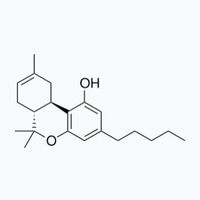

Dislcaimer: The information provided on this page is not intended to promote drug use. Many of the substances mentioned are illegal under domestic and international law and possession of these substances is punishable by law. Never assume that a substance is safe. Ecstasy pills (extasy, XTC, molly) are expected to contain MDMA but concentration, purity and adulteration vary greatly, even if aquired from the same source or if bear seemingly the same characteristics. Chemical Safety sp. z o.o. strongly advises against the use of any psychoactive substance – legal or illegal. Consuming psychoactive substances is always an avoidable risk to your health.